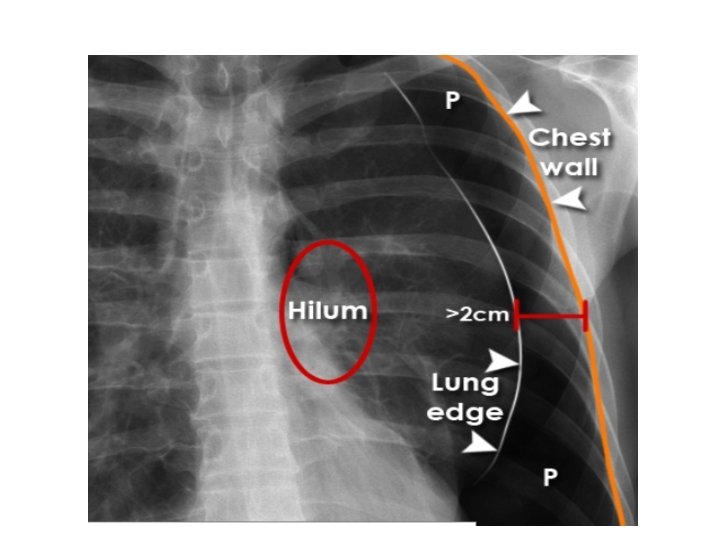

• • • plain Chest film 1 name , date of exposure 2. Lung apex. . 3. trachea. . 4. hilum. . 5. heart. . 6. diaphragm. . 7. cost phrenic angles. . 8. lung fields 9. Bones. . ribs, clavicle, scapula 10. soft tissue. Neck , breast, gas under diaph.